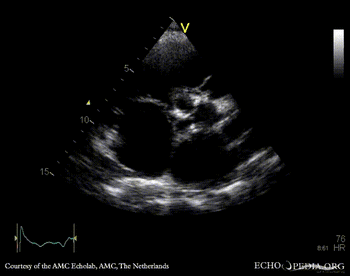

E00437.gif E00438.gif

A4CH: enlarged atria and ventricles A3CH: severe aortic and mitral regurgitation